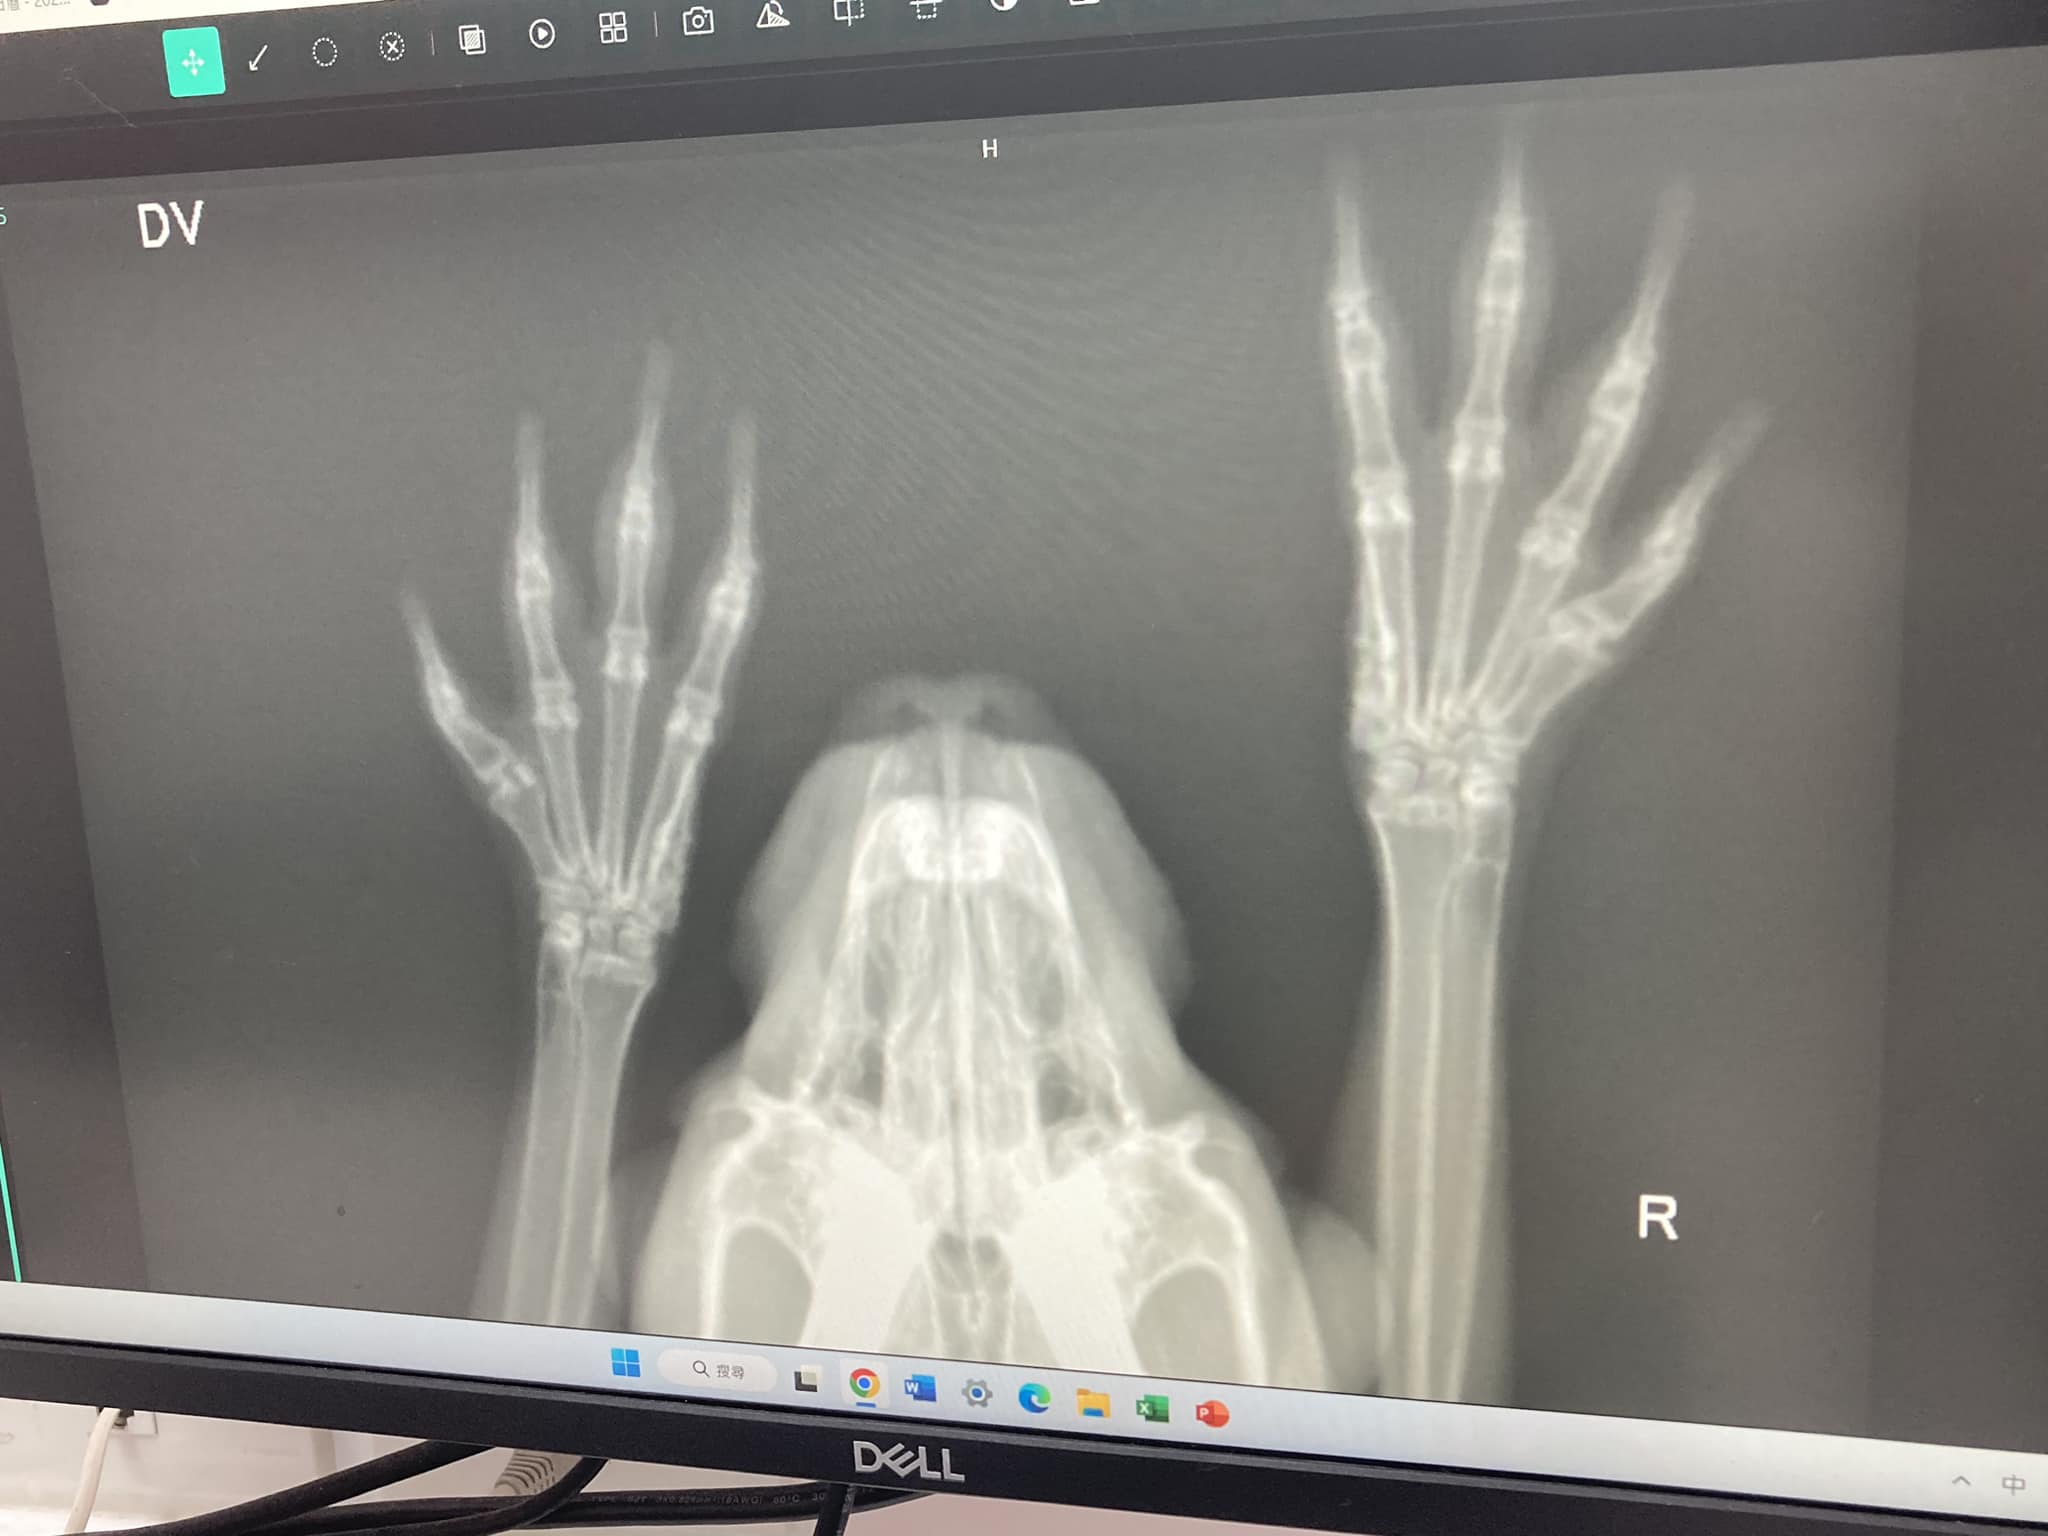

最近某次的放風時,突然聽到碰的一聲,然後女鵝就很生氣的躲在沙發下面跺腳,一連跺了好幾下。後來敏銳的爸爸就發現她變得不太愛出來放風,也發現她的飛奔中變得小心翼翼的,而後爸爸就決定帶她檢查一下。檢查結果是從x光照看不出任何問題。可能是嚇到吧⋯⋯但她真的很可愛,所以看她每次小心翼翼的樣子就很心疼。趕快變回原樣吧,小女兒!

最後健檢時間: 2023/6/19

健康;2023/6/19結紮;2023/6/11初次健檢,有螨蟲,腳有輕微疥癬,診間點藥,年紀約為3歲以內,牙齒狀況不錯